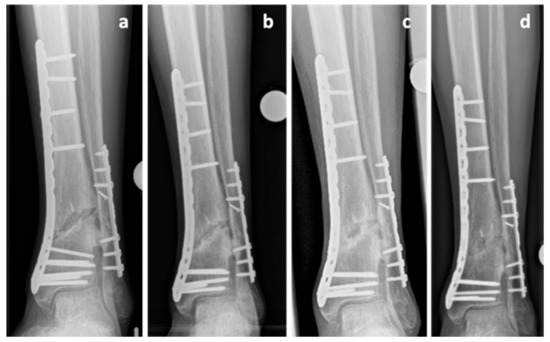

A 67-year-old Caucasian male patient (body mass 87 kg; height: 182 cm; BMI: 26.3 kg/m2) presented with a grade 1 open fracture of the right tibia and fibula (AO 43B2.2) and a grade 2 open fracture of the left tibia and fibula (AO 43B2.2) after jumping off a burning bus. He was initially treated with external fixators, and a few days later, ORIF and double-plate osteosynthesis (distal tibia LCP Plate, 3.5 LCP plate, single crews, DePuy Synthes, USA) on both sides (Figure 5a) were performed. While the left side showed regular bone healing, the radiological imaging of the right side revealed no signs of bone healing in serial radiographs. These findings were accompanied by persistent pain and the patient was diagnosed with an atrophic delayed union of the tibia, four months after the injury. NSAID medication was stopped, treatment of diabetes mellitus was optimized, and the decision to start teriparatide treatment was made. However, no progress in bone healing was observed. The double plate osteosynthesis was considered to be too rigid and, therefore, compromising fracture healing. Revision surgery was performed at the presence of an atrophic nonunion 9 months postoperatively with removal of the anterior tibial plate and autologous cancellous bone grafting (Figure 5b,c). Initially, there was no suspicion of an infection and therefore the original medial osteosynthesis was left in situ, no extensive debridement was performed. The intraoperative biopsies showed an osteomyelitis with peptostreptococcus species. Antibiotic treatment was initiated and continued as suppressive therapy. The teriparatide therapy was continued until signs of clinical healing and radiologic signs of bone union were achieved 18 months after the initial injury (Figure 5d,e). P1NP increased by 100% and CTX increased by 82% during teriparatide therapy indicating increased bone activity. The hardware was removed 24 months after the injury (Figure 5f). The intraoperative biopsies taken at the time of the hardware removal were negative, and the antibiotic therapy was discontinued.

Figure 5. Case 5, x-rays showing the postoperative outcome after initial treatment of grade 1 open tibial and fibular fracture (a), after partial hardware removal (anterior tibial plate) and autologous cancellous bone grafting at the presence of an atrophic tibia nonunion 9 months after trauma (b,c) and after achieving bone union 18 months after the initial injury (d,e). Final result after hardware removal 24 months after trauma (f,g).